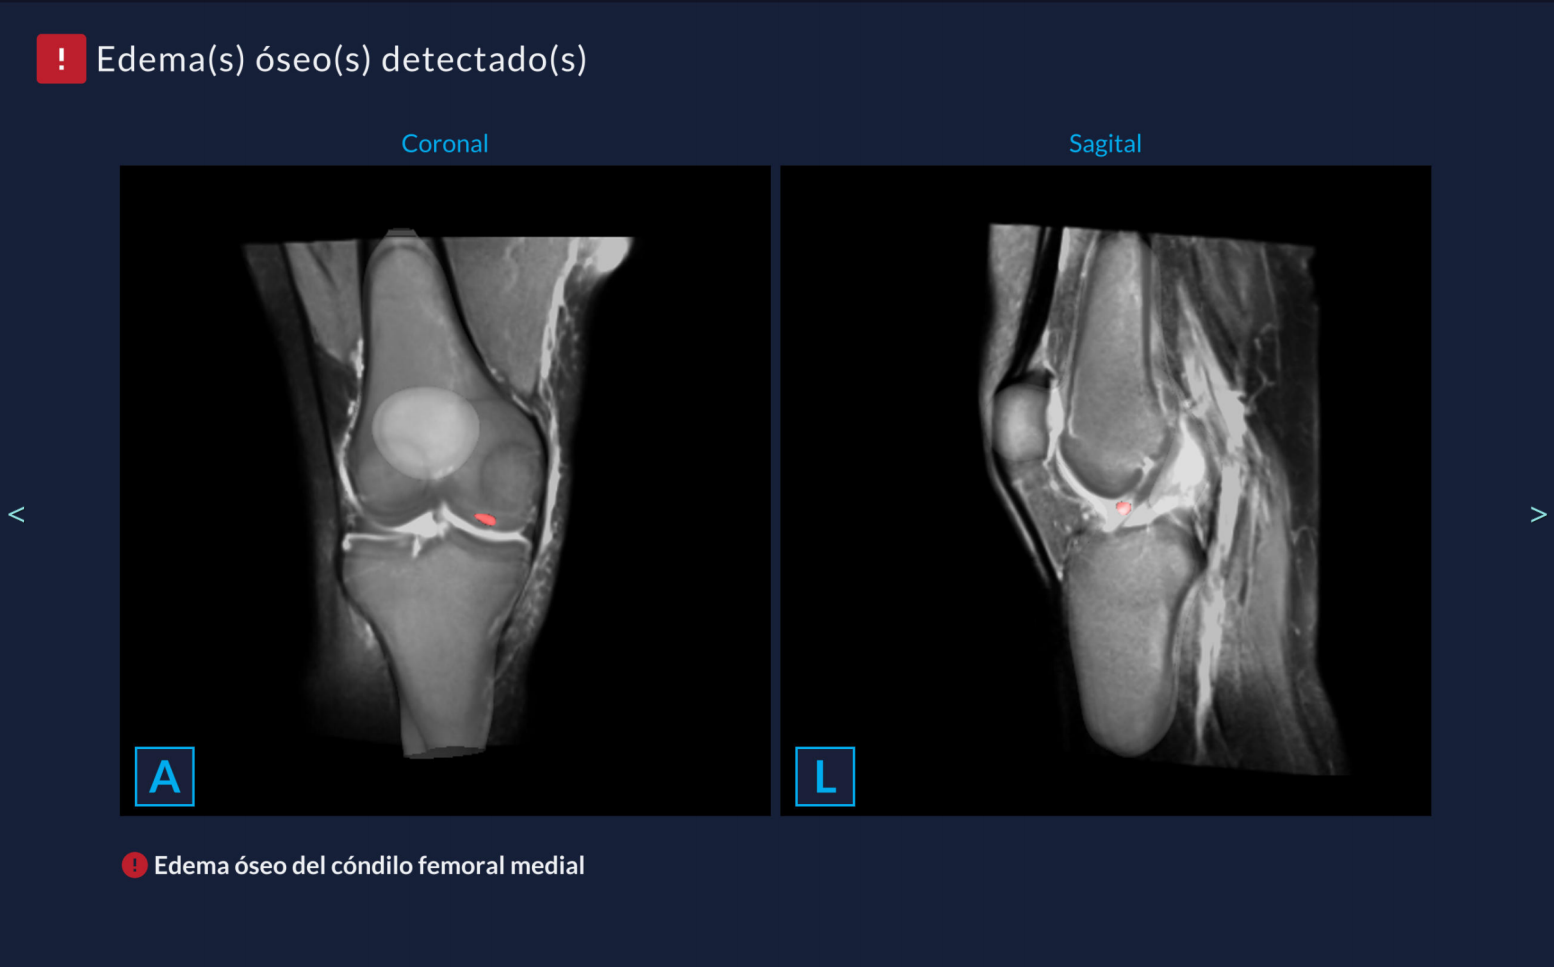

IA para Resonancia Magnética de Rodilla – KEROS

KEROS es una solución de inteligencia artificial diseñada para la asistencia diagnóstica en resonancia magnética de rodilla. Detecta y caracteriza lesiones musculoesqueléticas con alto nivel de confiabilidad clínica.

Detección de lesiones de ligamentos, meniscos y cartílagos.

Generación automática de informe precargado.

Más de 30 algoritmos entrenados con +22,000 estudios multicéntricos.

Incremento clínico: +20% sensibilidad diagnóstica en ligamentos.